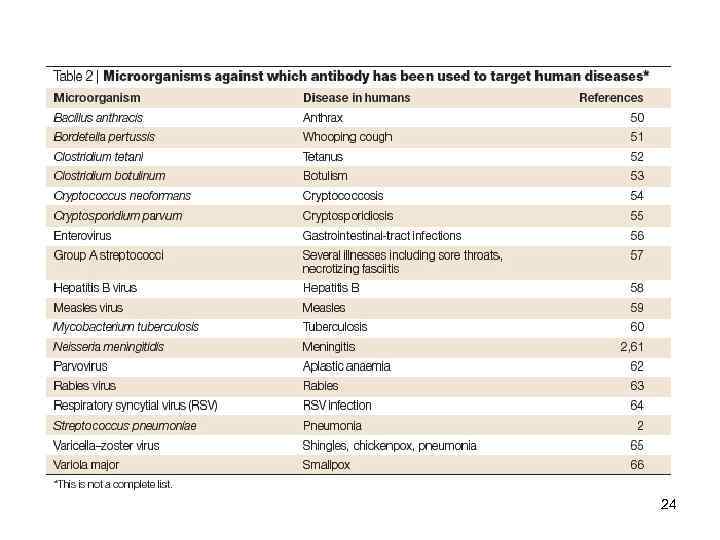

Функции АТ Passive antibody therapy for infectious diseases Arturo Casadevall, Ekaterina Dadachova & Liise-anne Pirofski Nature Reviews Microbiology 2, 695 -703 (September 2004) 20

Функции АТ Passive antibody therapy for infectious diseases Arturo Casadevall, Ekaterina Dadachova & Liise-anne Pirofski Nature Reviews Microbiology 2, 695 -703 (September 2004) 20